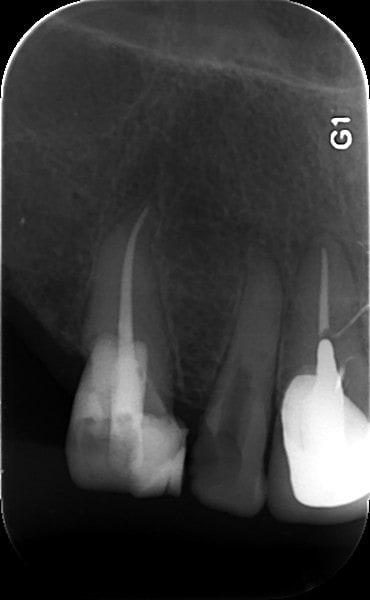

Cette semaine, j'ai galéré deux séances de 30 min pour traiter une incisive latérale maxillaire complètement calcifiée... J'ai essayé le forêt pilote, puis j'y suis allé carrément à la fraise diamentée fine pour rejoindre une portion de canal non oblitérée plus apicalement...

Quid du traitement d'une molaire nécrosée et complètement calcifiée?

http://www.endoexperience.com/pro_newsMar02.html

http://www.theendoblog.com/2007/12/finding-calcified-canal.html